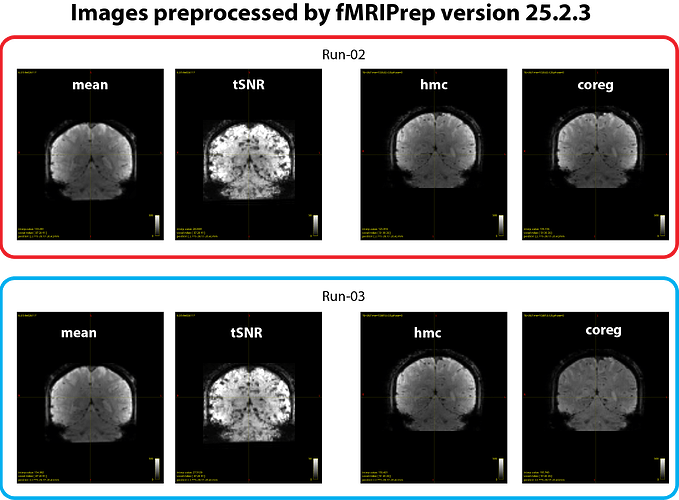

We suspected whether updating the fMRIPrep version would help. When we rerun the same analysis using ver 25.2.3, we found that a degree of inter-run inconsistency in *_desc-coreg_boldref.nii.gz images became much less compared with output from ver 24.1.1. However, perhaps some of the differences may still exist in this case, although it looks much better (see figure 3 below).